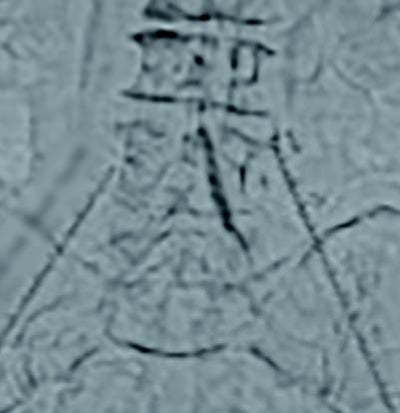

両側橈骨動脈より順行性に両側CIAにガイドワイヤーを通過させた。病変は偏心性石灰化でバルーン拡張により血管破裂のリスクがあることからVBXステントグラフト7.0 × 79 mm(6 Fr)を選択した。両側橈骨動脈からのアプローチにより(図4)スコアリングバルーンによる前拡張後(図5,6)、VBXステントグラフトを留置し(図4,7)、後拡張として高耐圧バルーン8.0 × 40 mmでキッシングバルーンテクニック(KBT)を行った(図8)。この際に迷走神経反射により心拍数が39回/分となったことから、これ以上の径での拡張は危険と判断し、手技を終了した。VBXステントグラフト留置後(図9)と術後造影(図3)では良好な血流が確認された。